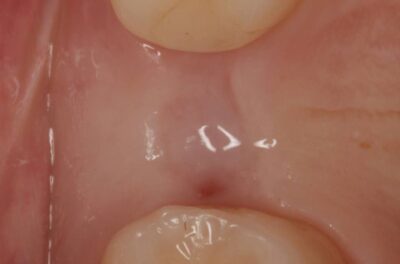

Специализация: терапия(эндодонтия), ортопедия, имплантология.